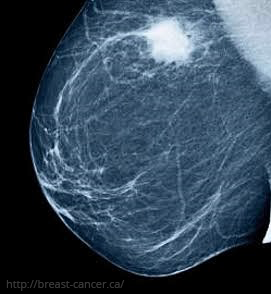

Mammography is considered the gold standard for evaluating breast conditions. It is not recommended before the age of 30–35 due to the sensitivity of younger breast tissue. Starting at age 40, annual or biennial mammograms are advised for early detection of breast cancer.

- Combined Approaches: Combining mammography with ultrasound enhances diagnostic accuracy, offering better results by compensating for the limitations of each individual method.

By utilizing these imaging techniques appropriately, breast cancer can be detected early, increasing the likelihood of effective treatment and improved outcomes.